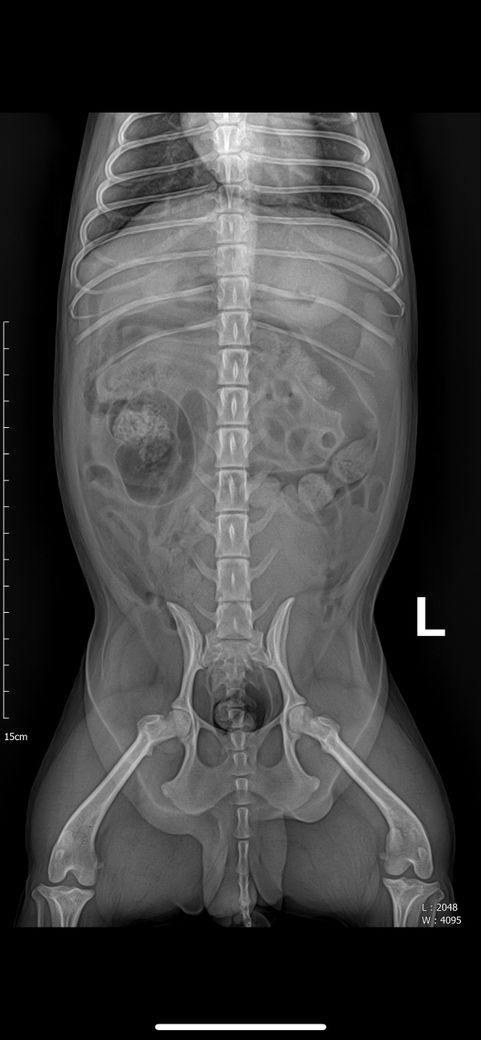

강아지 엑스레이에 문제점 있는지 봐주세요

강아지 엑스레이 문제 되는 곳 있는지 봐주세요 심장 크기랑 간이나 등등 문제 되는 곳이 있는지 궁금합니다 병원에선 문제 되는 곳 없다고 하시긴 했는데 조금 더 확실하게 알고 싶어서요

안녕하세요. 박창민 수의사입니다. 크게 문제되는 부분은 없는 거 같습니다. 또한, 엑스레이로는 정말 제한적인 정보만 얻을 수 있습니다. 더 많은 정보를 원하시면, 초음파 검사를 받으셔야 합니다. 감사합니다.

주치의의 판단이 옳은것으로 보입니다. 다만 좌측 슬개골의 내측 변위 양상 즉, 슬개골 탈구 상태가 있으니 이 부분에 대해 상담받으시고 수술 결정하시기 바랍니다.